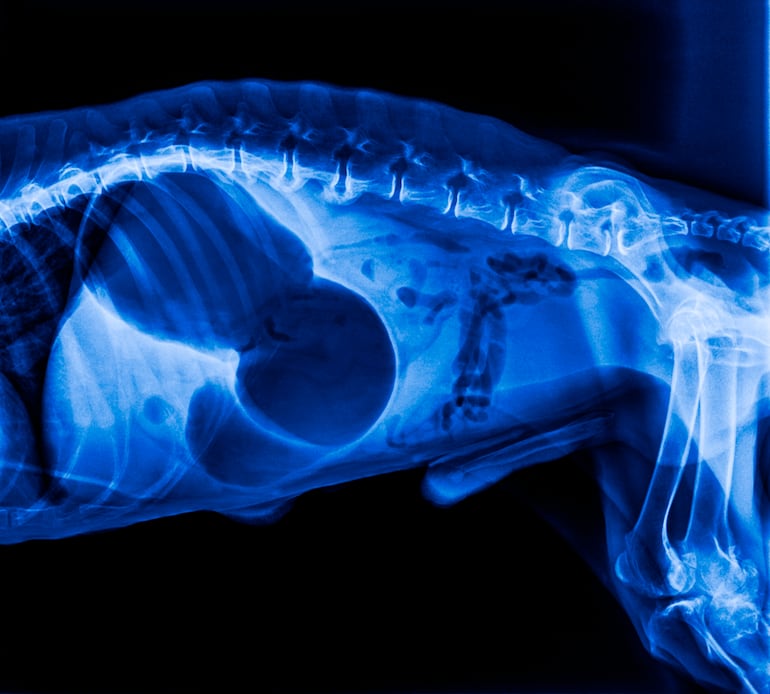

La hinchazón abdominal en perros es un motivo frecuente de consulta. A veces se trata de gas pasajero o de una indiscreción alimentaria (robó comida, cambió el balanceado, tragó aire). Pero en otros casos es el primer aviso de un cuadro que avanza rápido: la dilatación-torsión gástrica (conocida como “torsión de estómago” o bloat), una emergencia que puede comprometer la circulación y la vida en pocas horas.

En la torsión, el estómago se dilata y puede girar, bloqueando entrada y salida de gas y alimento; además, compromete vasos sanguíneos. Por eso no es un problema “digestivo” más: es un problema sistémico.

También hay otras causas relevantes: obstrucción por cuerpo extraño (juguetes, huesos, telas), ascitis por problemas hepáticos o cardíacos, hemorragia interna, pancreatitis. Varias requieren atención rápida aunque no haya torsión.